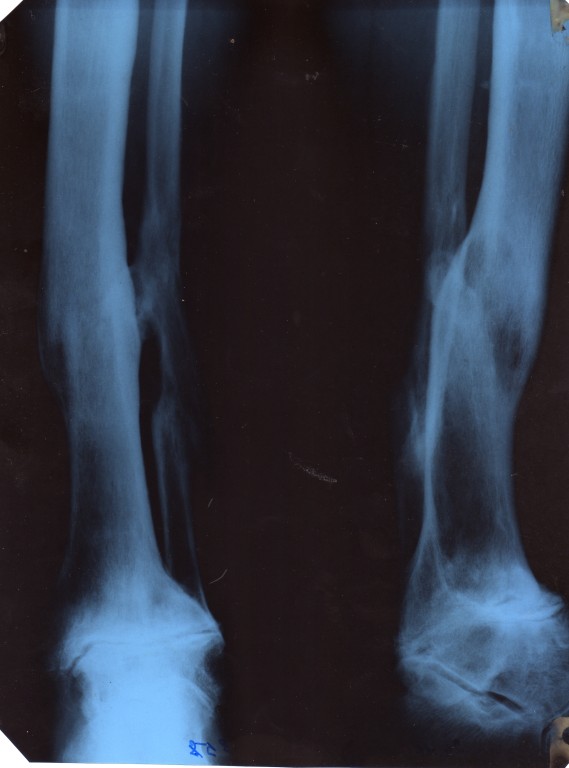

Серьёзное повреждение нижней конечности ( нога попала под приводной ремень механизма ).

Прошло более 30 лет, сейчас травматолог пишет в диагнозе: фиброзный анкилоз голеностопного сустава, рекомендации опорная трость. Хирург:посттравматический ДОА голеностопного сустава3 ст. с резко выраженной контрактурой. О том, что существует артродез, узнал только в прошлом году, но по видимому мне он уже и не нужен, до пенсии немного осталось, да и в плане с флебологами: посттромбофлебическая болезнь, ХВН 2-3. По работе приходиться переносить хоть и не часто 3-4 раза за смену груз на плечах весом 30 - 40 кг до 100 метров и с ним же спускаться по крутой лестнице, что согласитесь при почти не шевелящемся суставе достаточно не ловко да иной раз и больно. Вопрос у меня консультативного плана. На некоторых форумах просто тактично уходили в сторону от ответа. Мне приходиться хоть и не постоянно, но услугами трости пользоваться. Как ортопеды рассматривают вопрос переноса груза, пусть даже и 30 -40 кг ( для здорового это ерунда, для меня ощутимо в плане болевом и отёчном )с точки зрения специалистов.Можно?, или необходимо избегать этих нагрузок, для избежания последствий в виде боли. Если нагрузок не избежать, то сколько килограммов можно. Подразумевает ли предписание травматолога - опорная трость, снижение нагрузок в виде переноса тяжестей, так как он конкретно не написал ограничить нагрузки. С ним встречаться часто из-за удалённости нашего посёлка нет возможности. Так же на работе переизбыток общей вибрации, можно ли мне работать в этих условиях, похоже, что она не хорошо действует на сустав. Заметил нет нагрузок и вибрации, чувствую себя нормально, как отработаю несколько смен, нога начинает болеть.

• Кликните для загрузки файла Копия img107 [1024x768].jpg